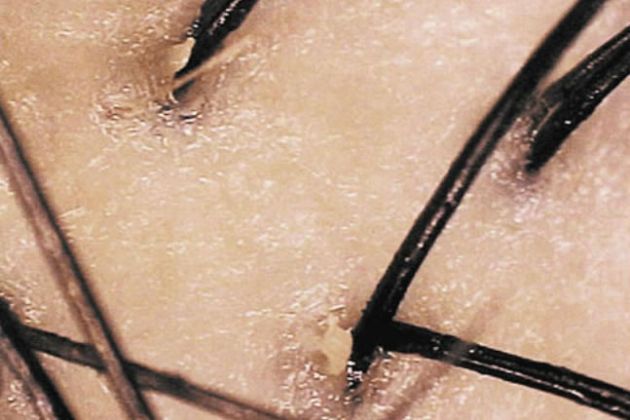

另一個可能導致頭髮油膩和頭皮皮膚乾燥的原因是脂溢性皮炎。這種慢性疾病往往是家族遺傳的,會導致皮膚髮癢、發紅、有黃色到白色的鱗片脱落。據信,這是由於油脂分泌過剩和一種酵母——馬拉色菌(malessizia)的刺激共同作用的結果。其他影響這種情況的因素有壓力、極端天氣和肥胖。痤瘡和油性皮膚似乎會增加這種問題的風險。